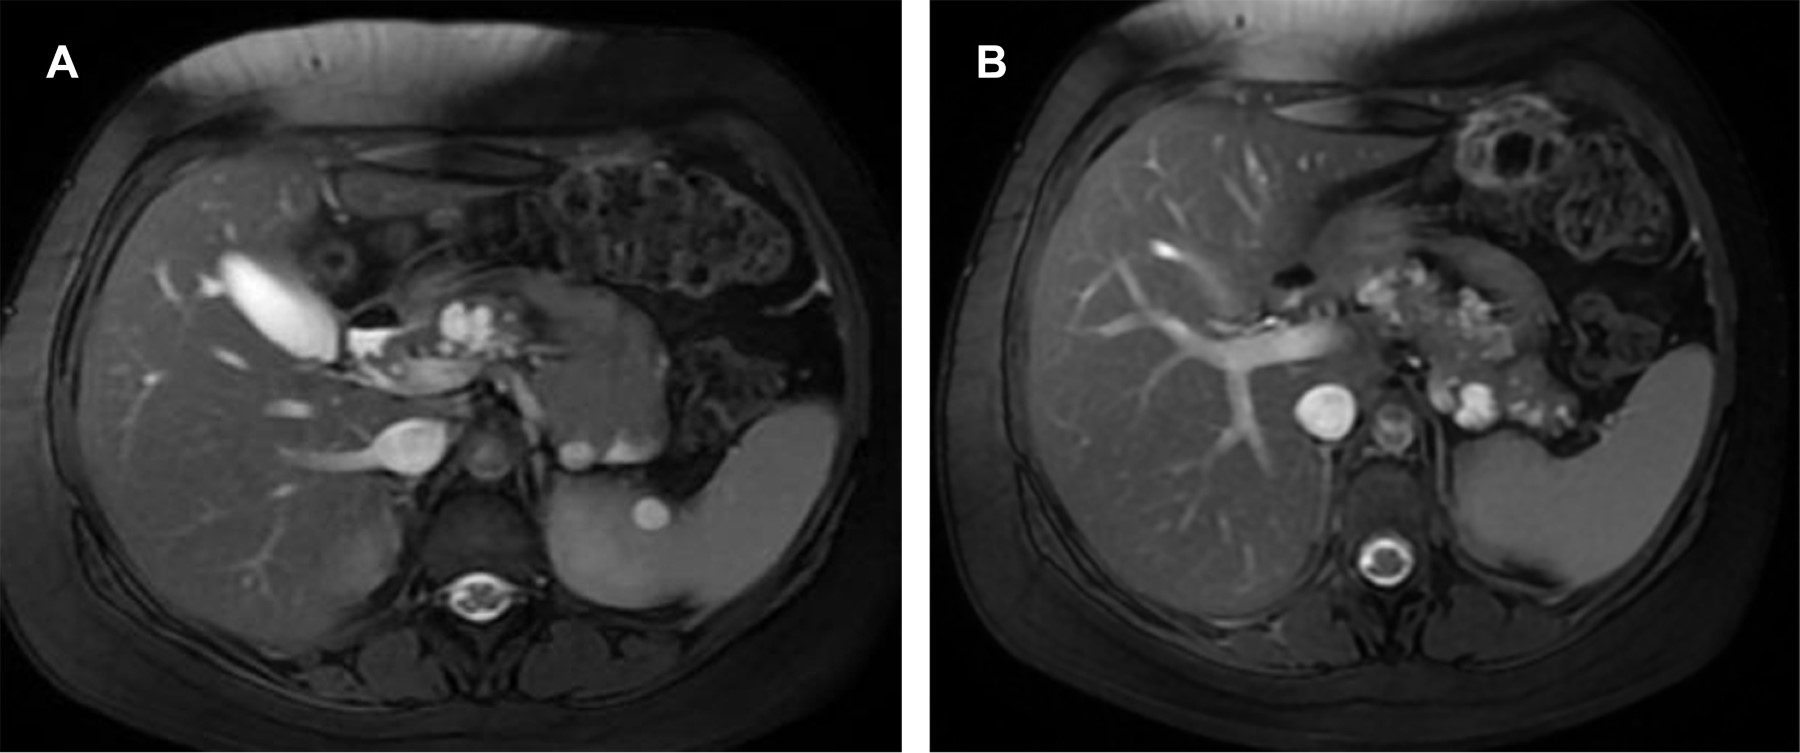

Mujer de 23 años con diagnóstico reciente de enfermedad de VHL y evidencia de hemangioblastoma en cerebelo que requirió tratamiento quirúrgico, acude asintomática para realización de RM abdominal como parte de sus estudios de tamizaje, en donde se evidenciaron quistes complejos en ambos riñones (Figura 1) y en páncreas (Figura 2).

Figura 1